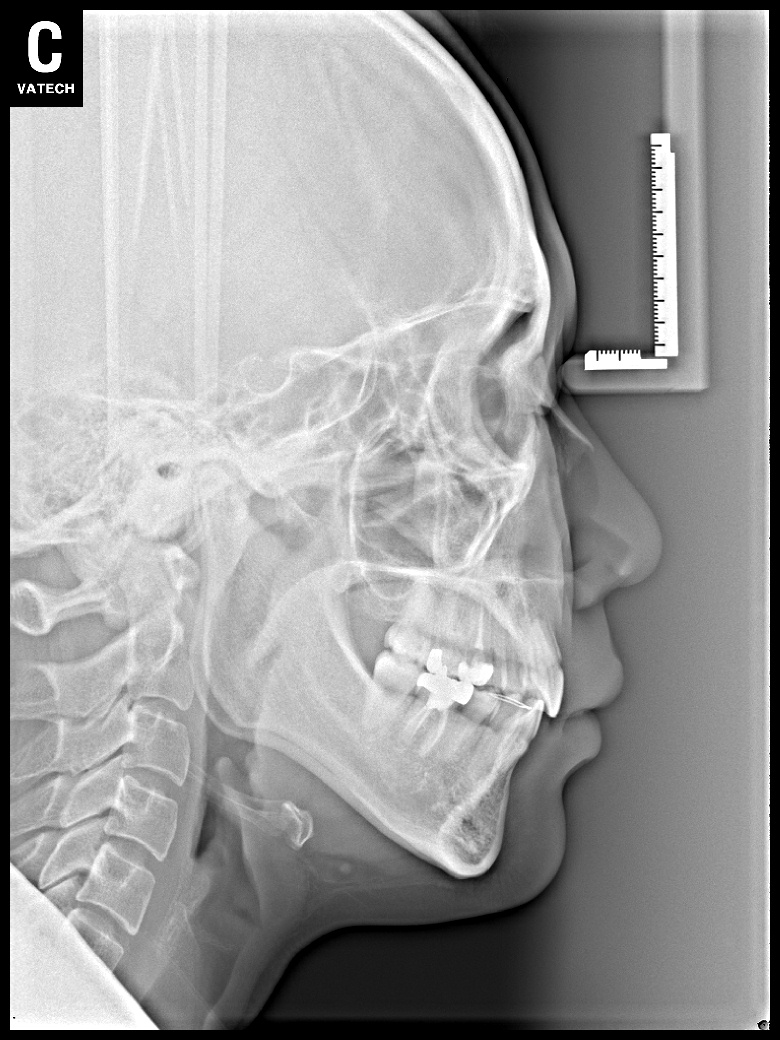

치료 전 사진입니다.